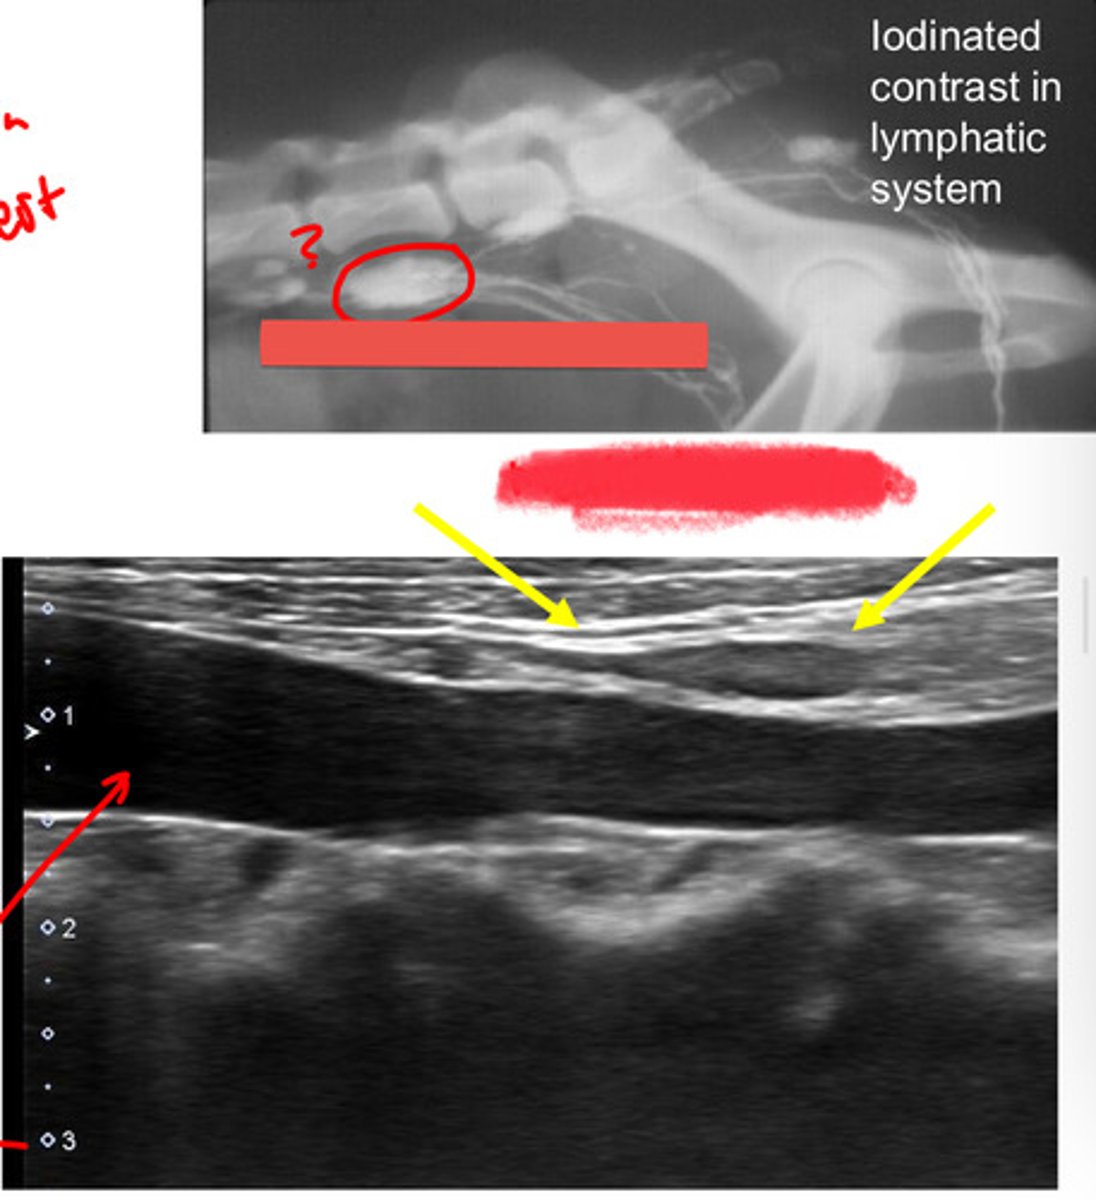

laterally adjacent to the external iliac arteries

location of the medial iliac lns?

most cranial in the pelvis (and LARGEST)

the medial iliac lns. are the most cranial or caudal in the pelvis?

lower urogenital tract, pelvis, and pelvic limbs

the medial iliac lns. drain what three areas?

-hypoechoic relative to surrounding fat

-hyperechoic relative to vessels

echogenicity of medial iliac lns.?

thin hyperechoic

what is the capsule of the medial iliac lns. echogenicity?

elongated oval shape

what is the shape of the medial iliac lns.?

medial iliac lns.

ID lymph node

medial iliac lns.

ID lymph node (hint: trifurcation near)